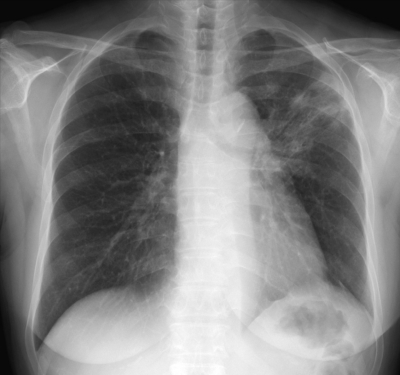

血液所見:赤血球 389 万、Hb 10.2 g/dL、Ht 32 %、白血球 5,800、血小板 25 万。血液生化学所見:総蛋白 6.7 g/dL、アルブミン 3.7 g/dL、総ビリルビン 0.3 mg/dL、AST 16 U/L、ALT 13 U/L、LD 273 U/L (基準 176〜353) 、クレアチニン 0.9 mg/dL、Na 143 mEq/L、K 4.4 mEq/L、Cl 105 mEq/L、CEA 4.8 ng/mL(基準5以下)。CRP 1.3 mg/dL。胸部エックス線写真と肺野条件の胸部CTとを別に示す。

最も考えられるのはどれか。

b. 放射線肺炎